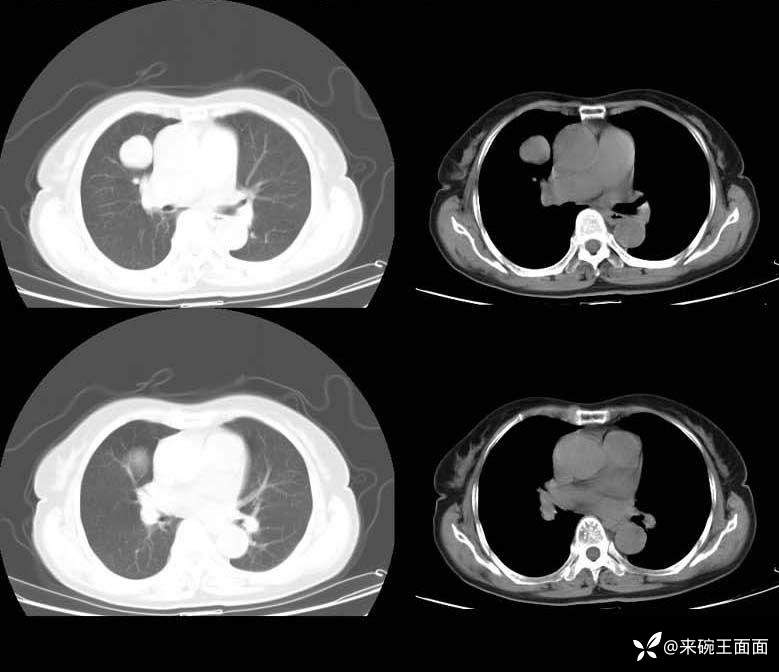

详情:右肺门类圆形肿块,边缘光整,增强扫描肺门侧可见一血管与肿块相连,且该病灶边界清晰,其密度均匀。对周围结构无明显影响。